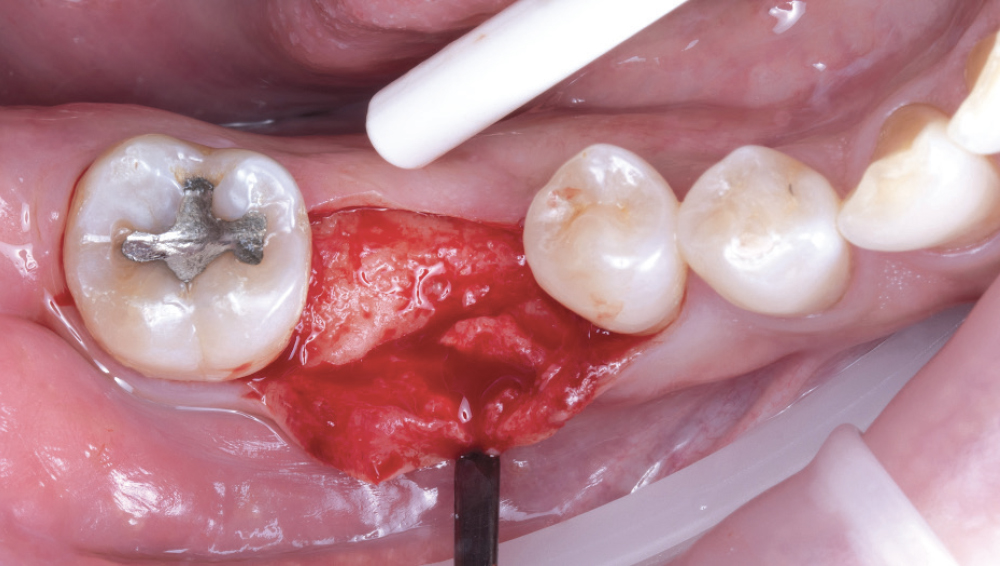

Reflection of Full-Thickness Flap While Preserving Keratinized Tissue

Figure 9: I opted to reflect a full-thickness flap while still preserving the band of keratinized tissue on the ridge, which is important for long-term peri-implant health, patient comfort, hygiene, and favorable soft-tissue esthetics around the final restoration.